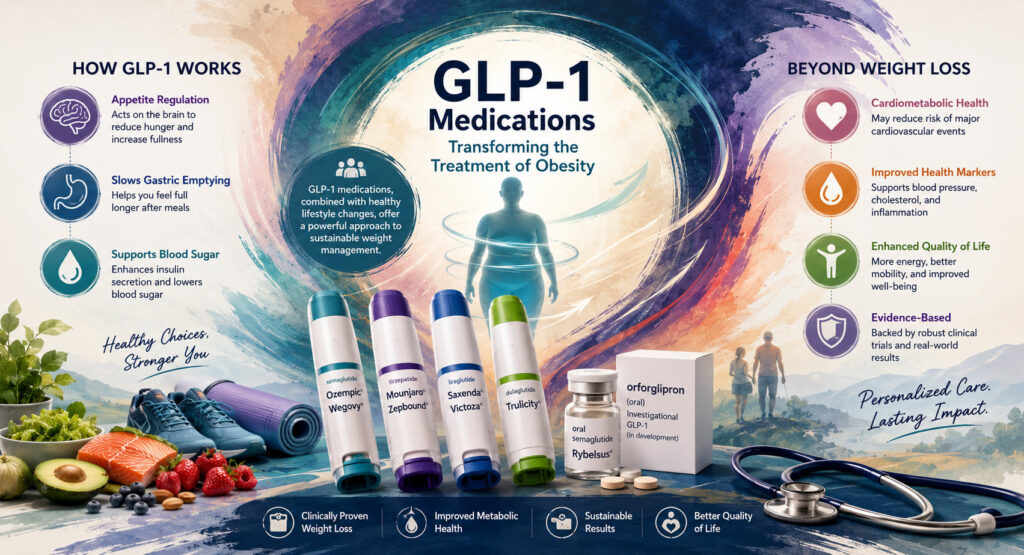

Tirzepatide GLP-1 medication may be most effective for weight loss

Monday, June 15 – GLP-1 medications are marketed to help you lose weight, but one may be better at it than the rest, according to a new meta-analysis from the University of Georgia.